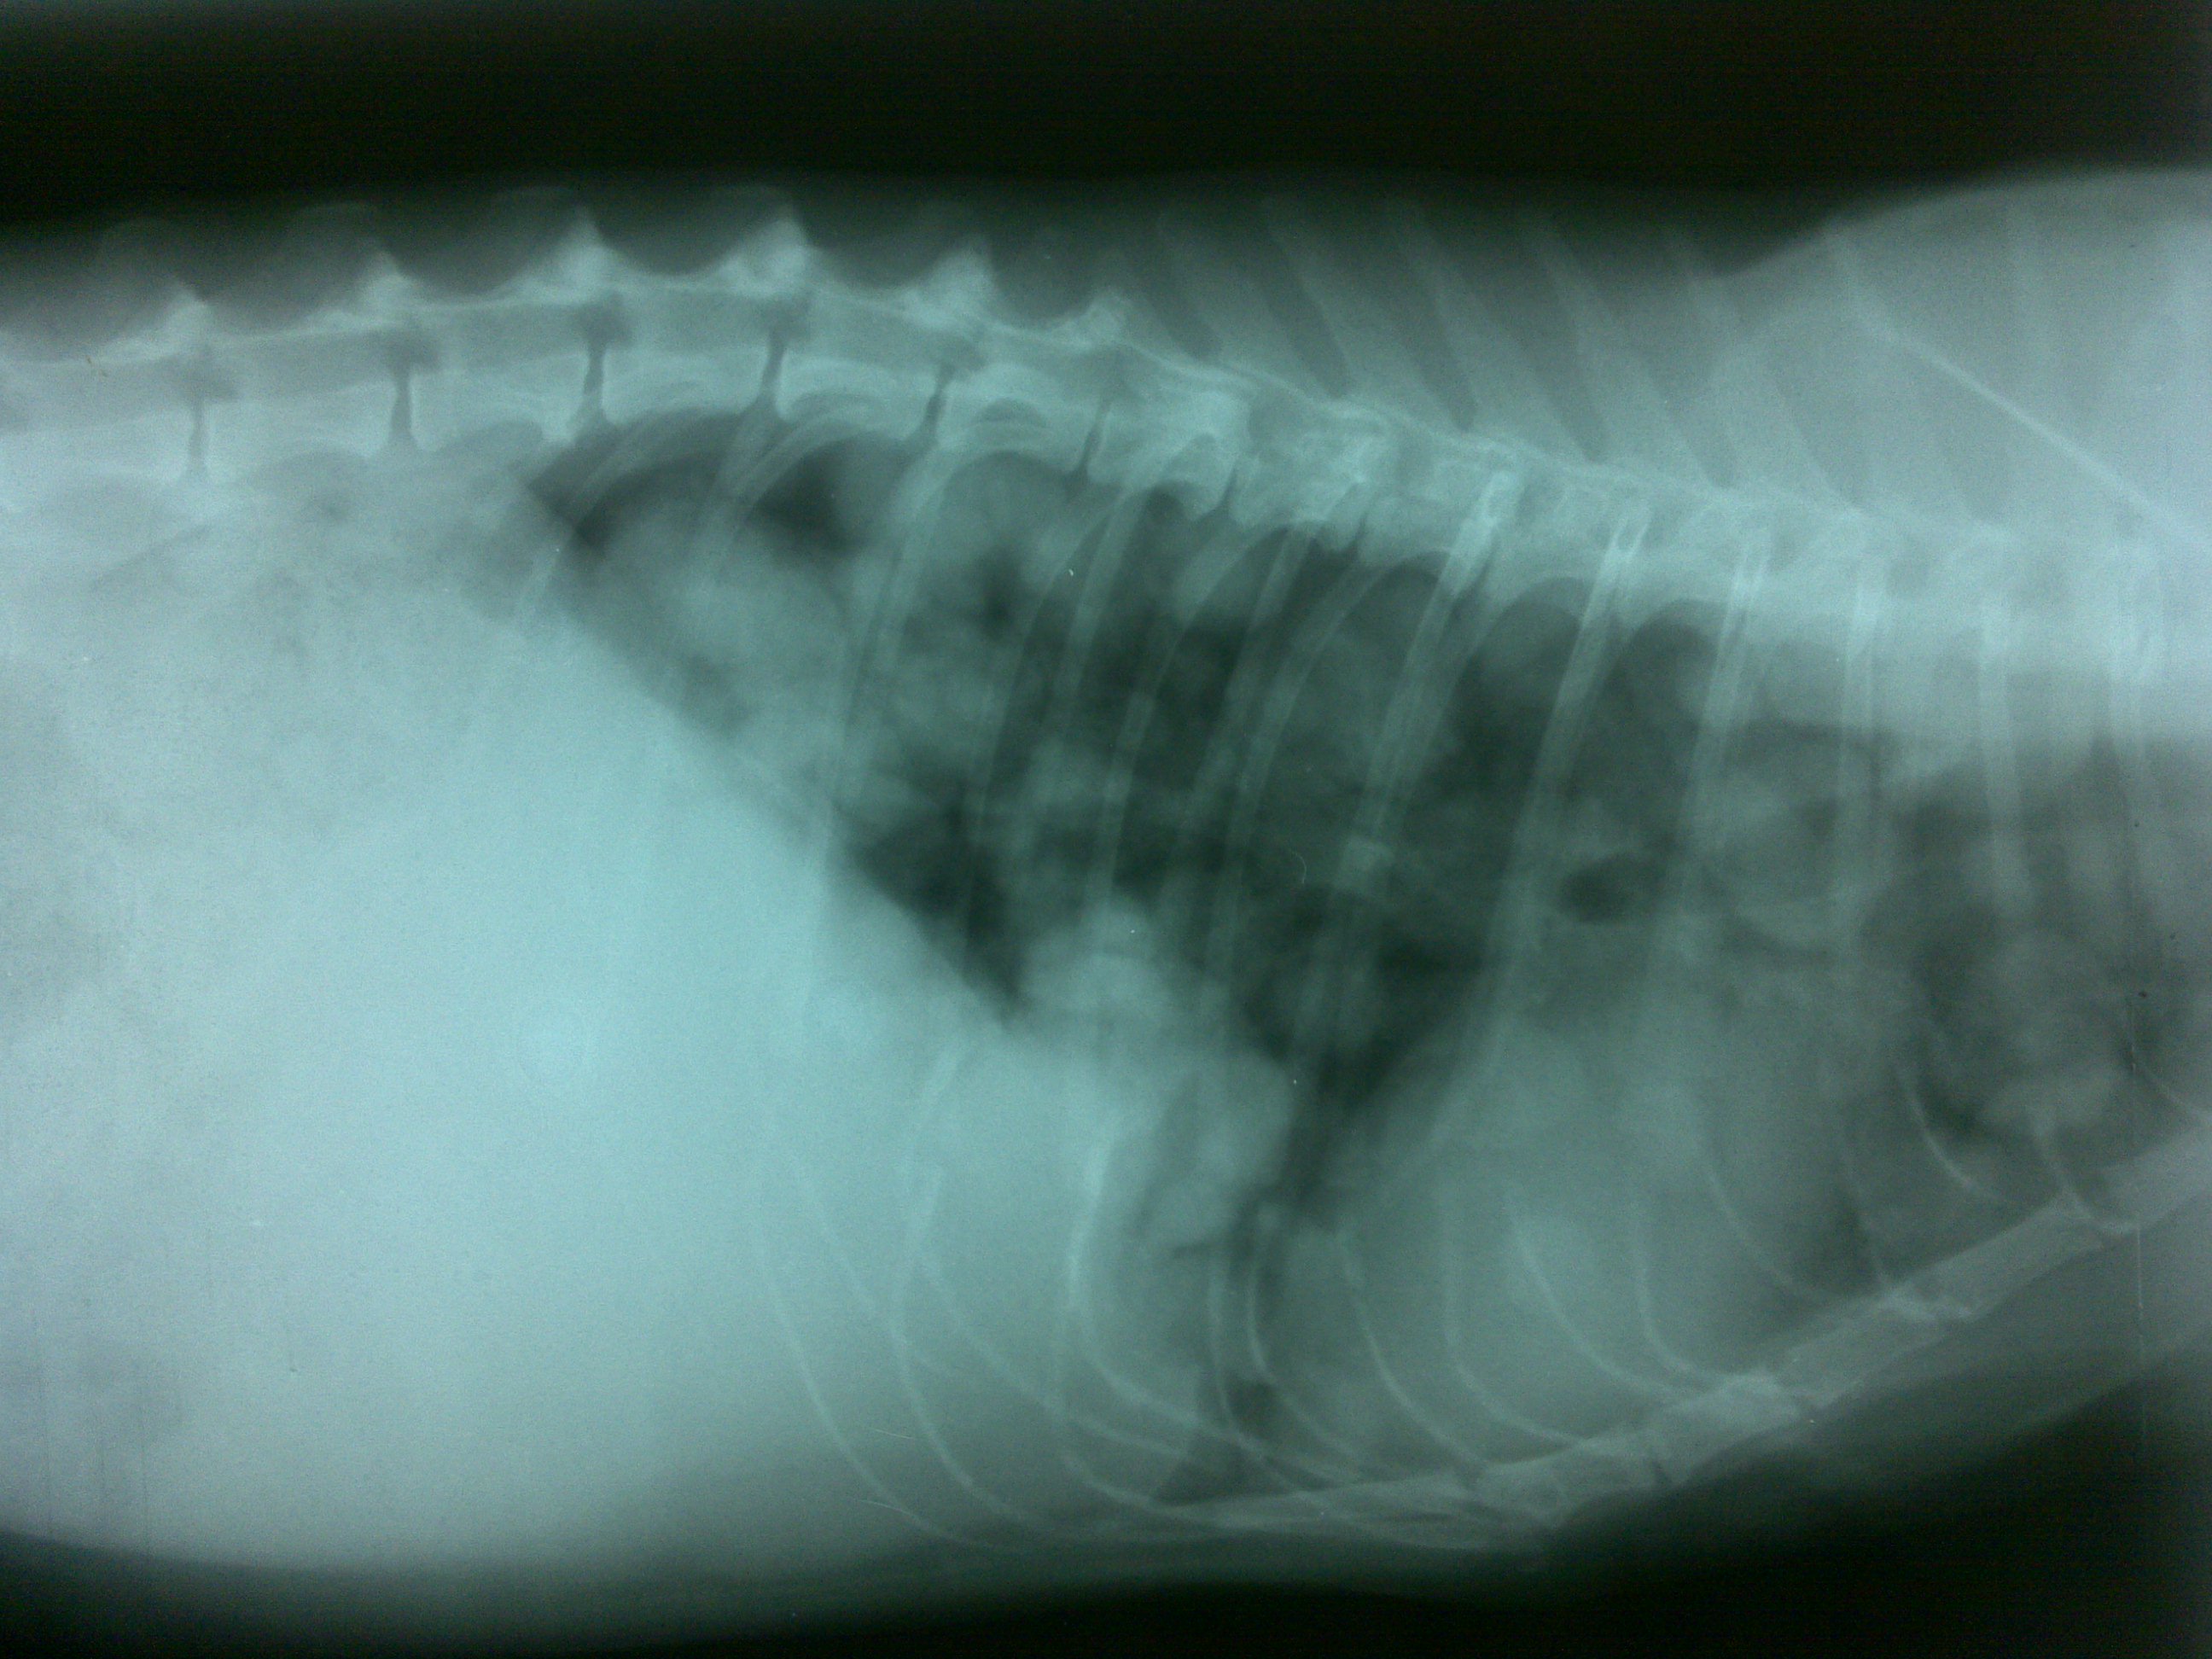

Neoplasia polmonare gatto

( diagnosticato definitivamente con supplemento citologico)